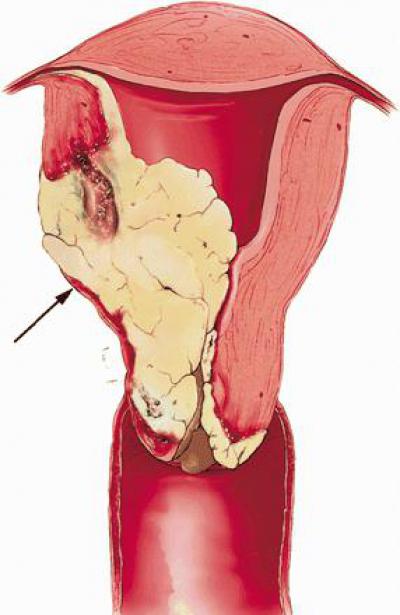

Description of macropreparation. In a single block, with a total size of 23 × 18 × 13 cm: uterus with a neck measuring 12 × 3.5 × 2.5 cm with a section of the vaginal wall 1 to 3 cm long, the right ovary measuring 6.5 × 4.7 × 2 .5 cm, a section of the rectum 18 cm long and a tumor formation measuring 22×17×10 cm. The tumor is represented by multiple thin- and thick-walled cysts with a diameter of 3 to 10 cm, filled with a clear yellowish-brown liquid. On the walls of the cysts, multiple nodular formations are determined on a wide base with a diameter of 1 to 4.8 cm, whitish in color with a bumpy, shiny surface, dense. On the section, the nodular formations are whitish in color, fibrous in appearance. The rest of the lining of the cysts is gray-pink, smooth, shiny. The mucous membrane of the vaginal portion of the cervix and vagina is gray-pink, smooth, shiny. The cervical canal is 5.

5 cm long, the mucous membrane of the cervical canal is grayish in color, trabecular in appearance. The thickness of the wall of the cervix is 1 cm. The uterine cavity is 4.8 cm long. The endometrium is gray, smooth, shiny. The myometrium is 1.7 cm thick. The right ovary in the section with multiple nodular formations with a diameter of 0.7-4.5 cm, gray-yellow, fibrous; fallopian tubes and left ovary are not defined. The mucous membrane of the large intestine is gray, with a characteristic folding, shiny, without ulceration. In the projection of the lower parts of the rectum – a gray area of compaction, up to 5 cm in diameter, without clear boundaries, tightly soldered to the vaginal wall. On the peritoneum of the Douglas space – two nodular formations with a diameter of 2 and 2.5 cm, whitish, dense. Microscopic examination: infiltrative tumor growth with invasion into the wall of the vagina, cervix and rectum to the submucosal layer. The tumor grows to the wall of the cervical canal throughout, grows into the myometrium.

Ki-67 is positive in single tumor cells (<1%). Conclusion: ESS of low grade of malignancy (G1), therapeutic pathomorphosis is not expressed (fig. 2, on the color insert). Figure 2. Histological structure of endometrial stromal sarcoma. Stained with hematoxylin and eosin. ×400. At the control examination 3 months after the operation, there were no signs of continued tumor growth.